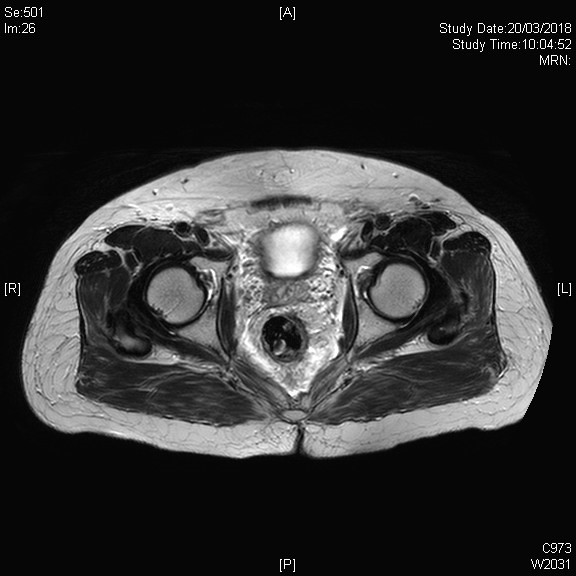

男性患者的盆腔一般都較女性患者狹窄

高BMI的患者